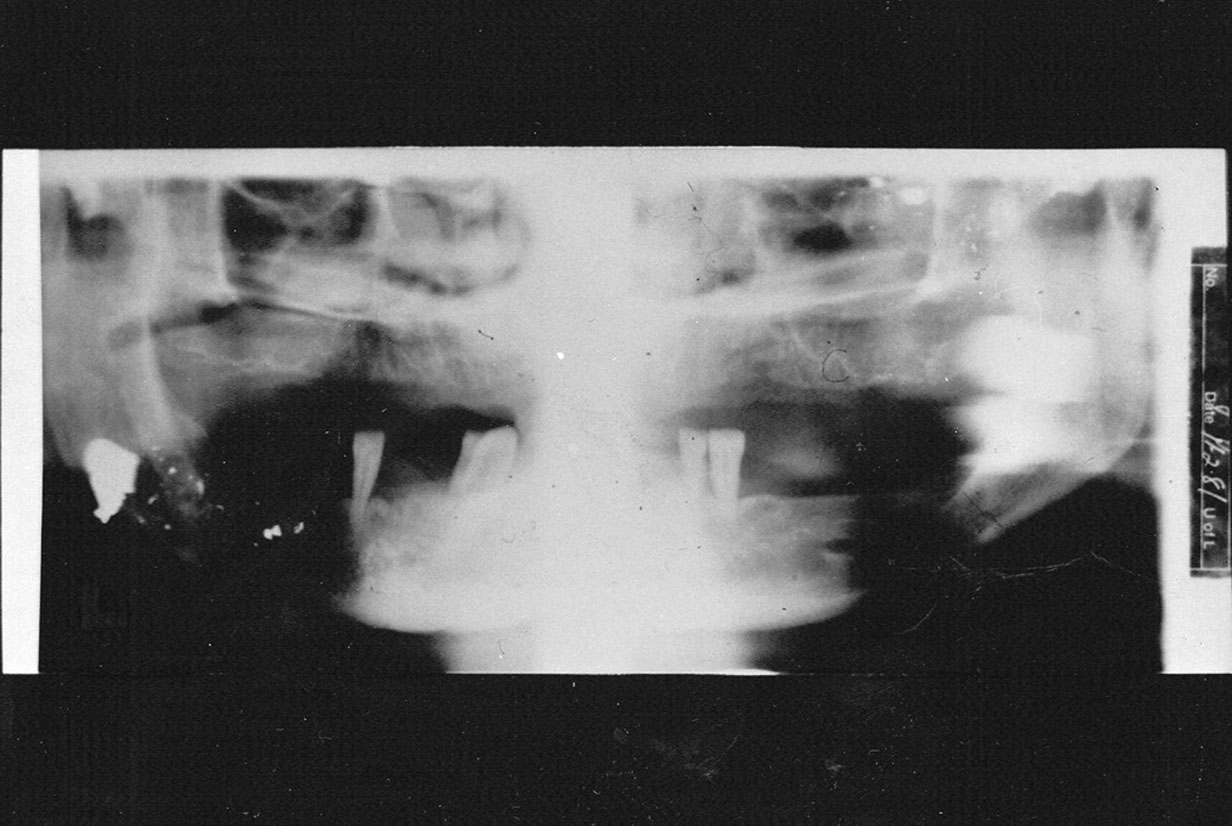

Chin/Head Position

If the patient’s chin is tilted downward, the arches will appear constricted. The condyles will appear closer together and may be cut off at the top of the film. The overall appearance will be that of a “Cheshire cat grin” due to the accentuated curve of Spee (Figure 21). If the patient’s chin is tilted upward, the image of the arches will be one of overall flattening or elongation. The condyles will be farther apart and may be cut off at the sides of the film. The general appearance is that of a wide “grimace,” as in Figure 22, due to a flattened curve of Spee.

Figure 21. Curve of Spee.

Figure 21